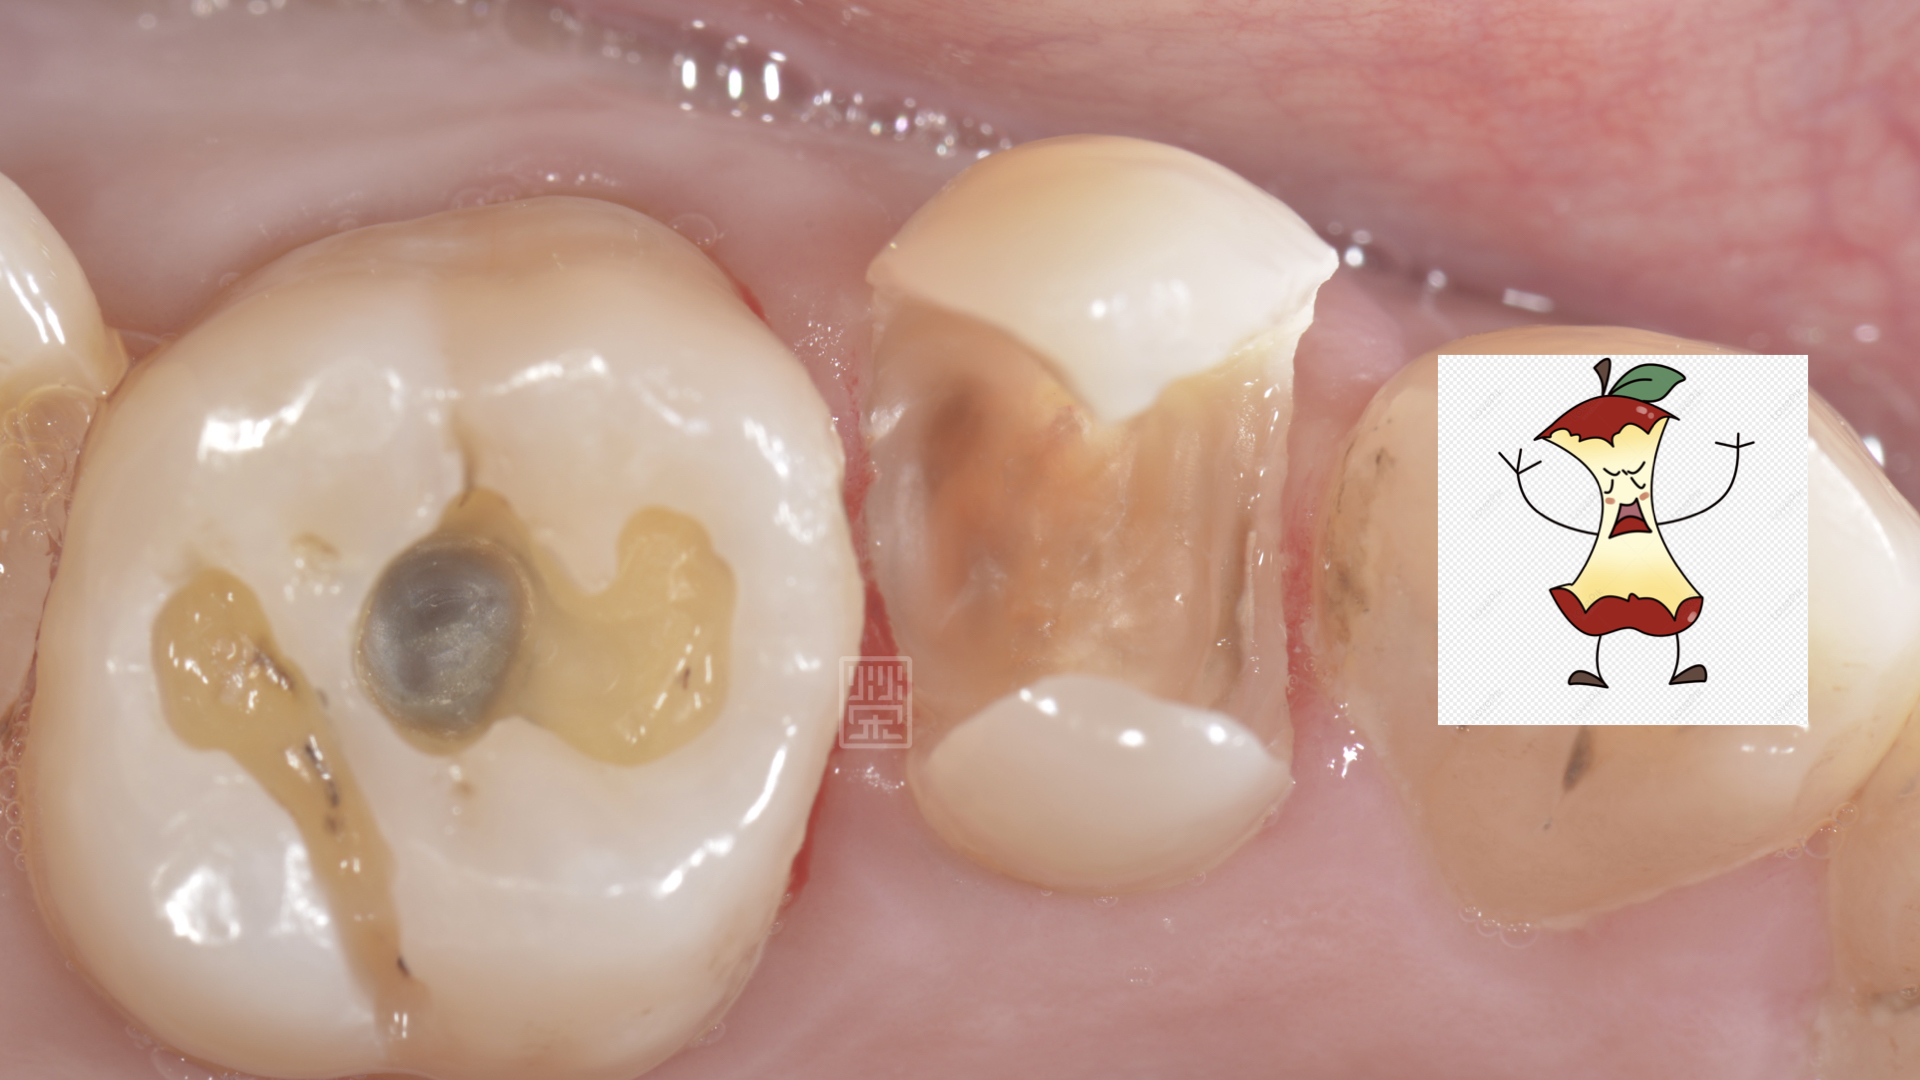

將舊填補物與蛀牙清除後,剩下兩片薄薄的齒質,看上去就像是卡通蘋果被咬一圈,首先先考量牙髓神經的健康性,X光與臨床檢查上,牙髓仍是健康的狀態,但是剩餘健康的齒質這麼少,要怎麼恢復牙齒的強度呢?

蛀牙拿乾淨後,很像蘋果卡通圖被啃一圈的樣子

另一個角度看清除蛀牙後的狀況